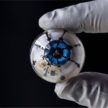

জেনেটিকসের উন্নতির ফলে শতভাগ দক্ষতার সঙ্গে নকশাকৃত শিশু পাওয়া সম্ভব বলে দাবি করছেন বিজ্ঞানীরা। সম্প্রতি চীনের বিজ্ঞানীরা মানুষের ভ্রণে জিনগত পরিবর্তন ঘটানোর দাবি করেছেন। তারা সমস্যার জন্য দায়ী একটি জিন ভ্রূণ থেকে সরিয়ে ফেলতে ব্যবহার করেছেন বিতর্কিত একটি পদ্ধতি । প্রযুক্তি ও ব্যবসা বিষয়ক ওয়েবসাইট বিজনেস ইনসাইডারে উঠে এসেছে সেই তথ্য।

জেনেটিকসের উন্নতির ফলে শতভাগ দক্ষতার সঙ্গে নকশাকৃত শিশু পাওয়া সম্ভব বলে দাবি করছেন বিজ্ঞানীরা। সম্প্রতি চীনের বিজ্ঞানীরা মানুষের ভ্রণে জিনগত পরিবর্তন ঘটানোর দাবি করেছেন। তারা সমস্যার জন্য দায়ী একটি জিন ভ্রূণ থেকে সরিয়ে ফেলতে ব্যবহার করেছেন বিতর্কিত একটি পদ্ধতি । প্রযুক্তি ও ব্যবসা বিষয়ক ওয়েবসাইট বিজনেস ইনসাইডারে উঠে এসেছে সেই তথ্য।

তবে চীনা বিজ্ঞানীদের মানব ভ্রূণ নিয়ে এ ধরনের পরীক্ষা-নিরীক্ষা করা থেকে সরে আসতে বলছেন যুক্তরাজ্যভিত্তিক একদল গবেষক। তাদের দাবি, বিতর্কিত যে পদ্ধতিটি ব্যবহার করে মানব ভ্রূণে জিনগত পরিবর্তন করা হচ্ছে, তা নিরাপদ কি না বা প্রযুক্তিগত কোনো ত্রুটি আছে কি না, সে প্রভাবগুলো খতিয়ে দেখার আগ পর্যন্ত এ ধরনের গবেষণা করা ঠিক হবে না। তারা বলছেন, বিশেষ জার্ম লাইন প্রক্রিয়ায় জিনগত যে পরিবর্তন আনা হচ্ছে তা বিপজ্জনক ও নৈতিকতাবিরোধী। এই পদ্ধতিতে মানুষকে তাঁদের কাঙ্ক্ষিত বা ইচ্ছানুযায়ী সন্তান নিতে উৎসাহী করবে। মানুষ তাঁদের কাঙ্ক্ষিত জিনগুলোই কেবল ভ্রূণের মধ্যে চাইবে। এতে কেবল ‘নকশা করা’ শিশু জন্ম দেওয়ার প্রবণতা বাড়বে।

এ শতকের বায়োটেকনোলজির সবচেয়ে বড় আবিষ্কার হবে জন্মের আগেই ঠিকঠাক করে রাখা বা নকশা করে রাখা শিশু ও সম্পাদনা করা মানুষের জন্মের ঘটনা। নকশাকৃত এ ধরনের শিশু হবে দারুণ চটপটে, রোগমুক্ত, শারীরিকভাবে দক্ষ। এই শিশু যে বৈজ্ঞানিক কল্পকাহিনির শিশুদের মতো হবে, তা না বললেও চলছে।

কিছু গবেষক এ ধরনের গবেষণার ফল অনৈতিক কাজে ব্যবহারের আশঙ্কা করলেও কিছু গবেষক মনে করছেন ক্যানসারের মতো কিছু রোগের চিকিৎসায় এ ধরনের গবেষণা কাজে লাগানো যাবে। নেচার সাময়িকীর এক প্রতিবেদনে বলা হয়েছে, চীনের গুয়াংজুর সান ইয়েতসেন বিশ্ববিদ্যালয়ের গবেষকেরা প্রোটিন অ্যান্ড সেল সাময়িকীতে গবেষণা সংক্রান্ত নিবন্ধ প্রকাশ করেছেন। গবেষণা কাজে নেতৃত্ব দিয়েছেন গবেষক জুনজিউ হুয়াং।

গবেষক জুনজিউ দাবি করেছেন, অকার্যকর ভ্রূণ ব্যবহার করে তাঁরা এই গবেষণা করেছেন যা শিশু হিসেবে জন্ম নিতে সক্ষম নয়। রক্তের সমস্যা বা বেটা-থ্যালাসেমিয়া তৈরির জন্য দায়ী জিনটিকে সিআরআইএসপিআর/ক্যাস ৯ নামের পদ্ধতিতে সম্পাদনা করা হয়েছে। এতে জিনের নির্দিষ্ট অংশ পরিবর্তন করে ফেলা সম্ভব হয়।